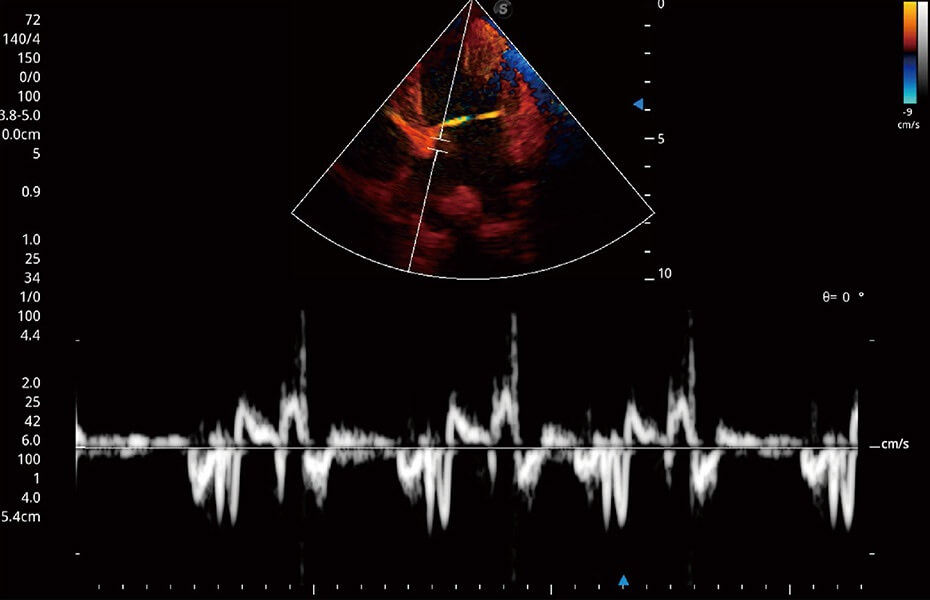

ProPet 60 作為一款高端臺(tái)式動(dòng)物超聲設(shè)備,為動(dòng)物醫(yī)生的日常診斷提供了一系列貼合動(dòng)物臨床需求、解決臨床實(shí)際問(wèn)題的高級(jí)成像功能。憑借全系列高清探頭,滿足醫(yī)生對(duì)腹部、心臟、生殖、淺表、肌骨等成像的所有需求,切實(shí)幫助您提升檢查效率,提高診斷信心。